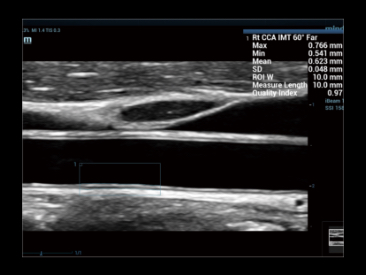

На изображении плечевой сустав: 1- Более подробная информация о мышцах; 2- Лучшее определение сухожильных волокон.